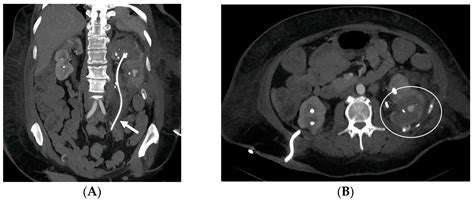

• Kidney Stones: These are the most frequent cause. A stone may become stuck in the ureter, causing a blockage and intense pain.

• Ureteral Strictures: Narrowing of the ureter caused by scar tissue or inflammation.

• Tumors or Growths: External pressure from a tumor in the pelvis or abdomen can compress the ureter.

4. Stent Placement: The stent is threaded over the guidewire and moved into the correct position. Once verified using X-ray imaging (fluoroscopy), the guidewire is removed, leaving the stent in place.